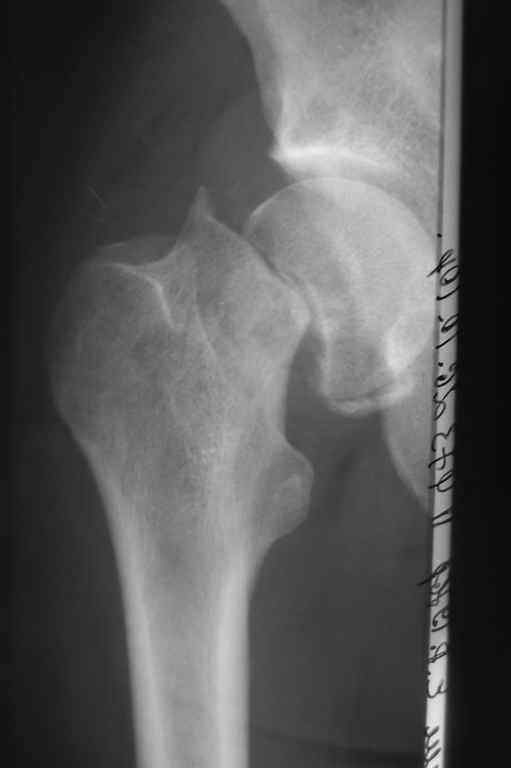

[Ortho] Застарелый перелом шейки бедра

Пациенту 34 года. Травма 10 недель назад. Стоит ли попробовать выполнить остеосинтез, либо сразу - эндопротезирование?